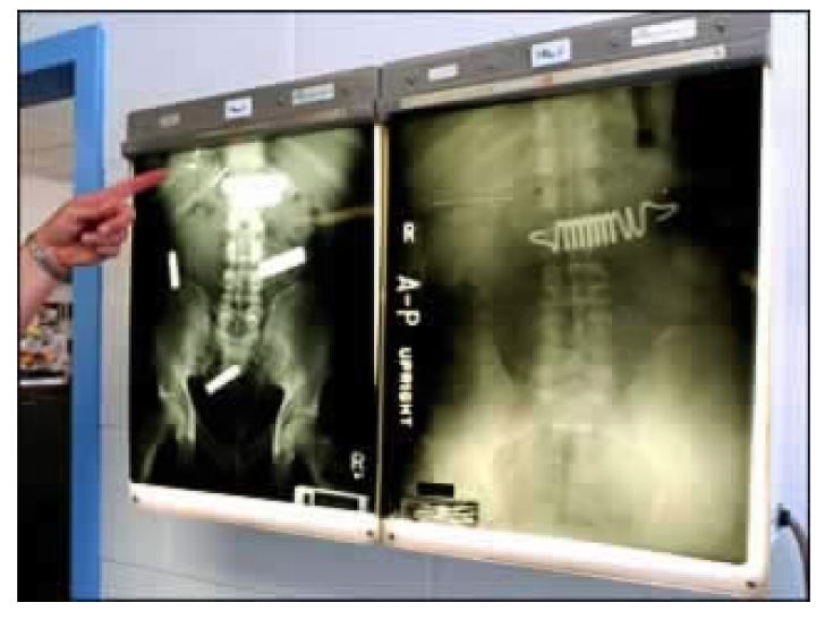

Algunos presos están dispuestos a tragar cualquier cosa para salir de la cárcel, por ejemplo, al hospital, incluso los resortes del colchón.